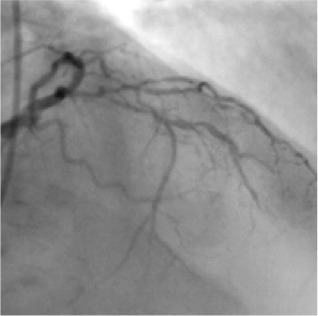

Based on this IVUS image, a large stent was deployed and the artery was opened and blood flow was restored.

Patient was discharged in 48 hours and resumed his normal job within 7 days. 1 year later, his stress perfusion scan is absolutely normal.